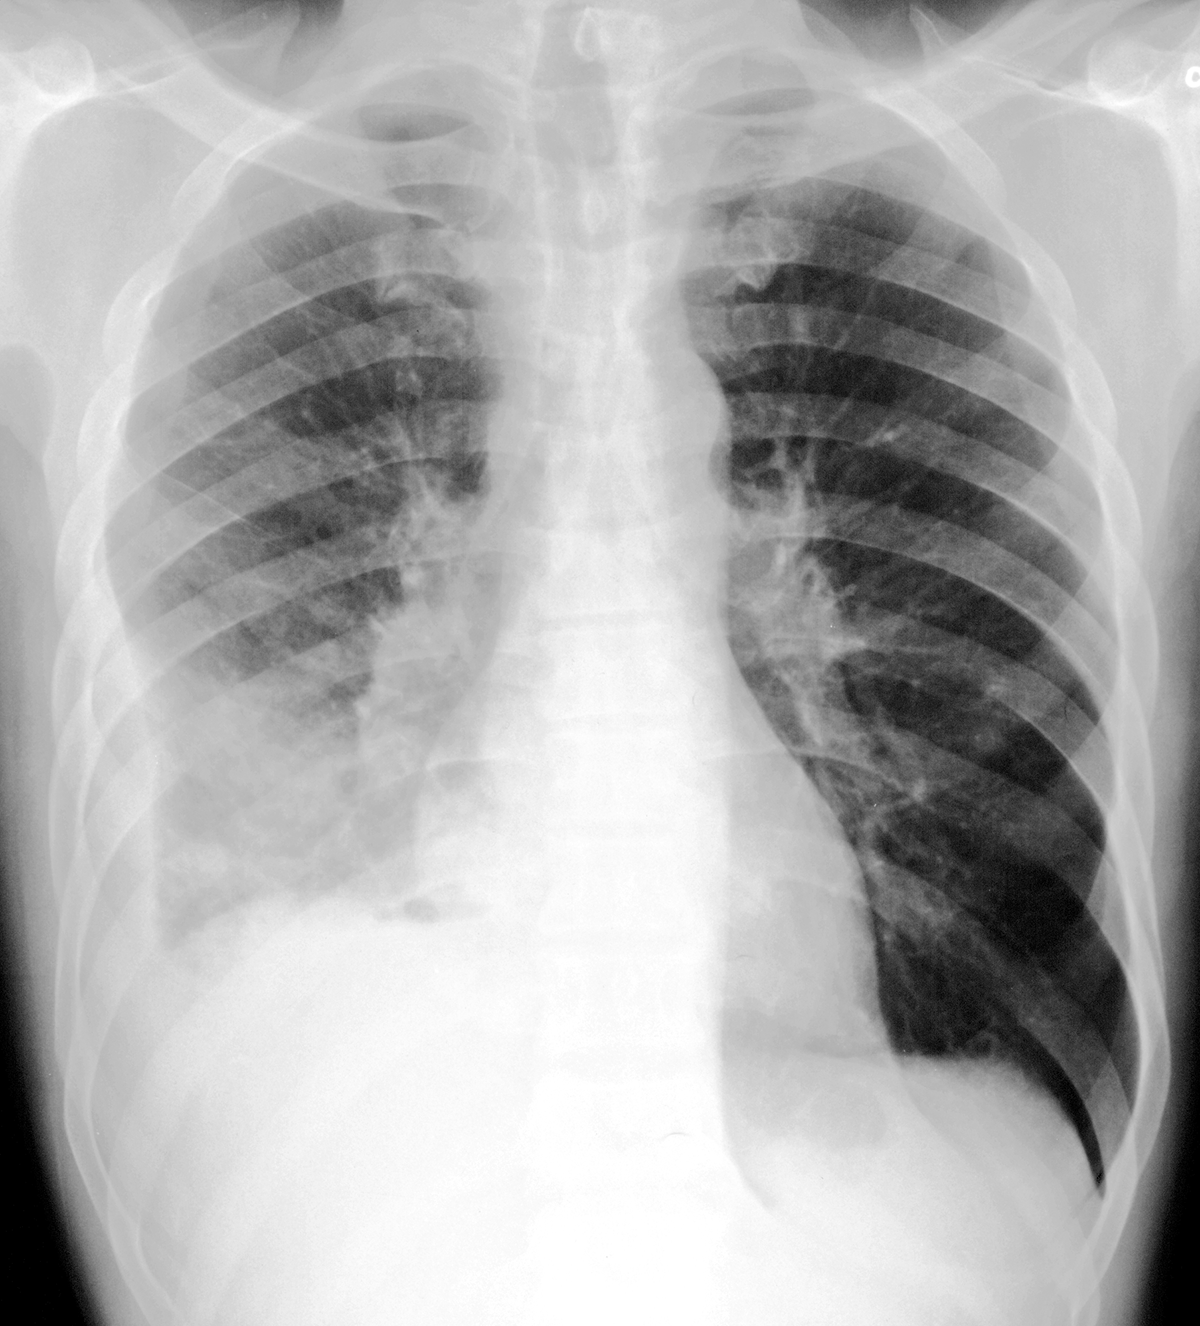

Topic 3

alternative diagnosis for effusion

Further Explanation: